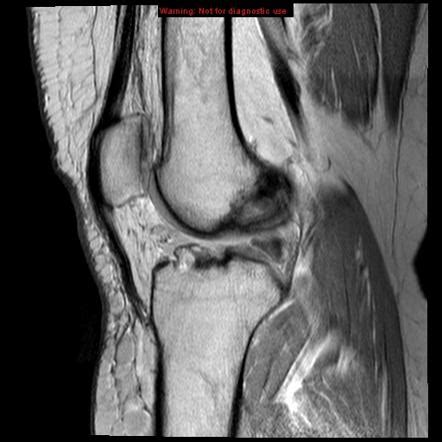

An acl tear is when the anterior cruciate ligament becomes partially or completely ruptured. Anterior cruciate ligament (acl) tears are a common injury to the knee, especially among athletes. The acl—the anterior cruciate ligament—is one of four main ligaments in your knee. When is acl surgery necessary? When the acl is torn, it's almost always due to at least one of the following patterns of injury in diagnosing an acl sprain, your doctor will want to know exactly how you hurt your knee.

How is a torn acl diagnosed? There are times when not everyone has every symptom of an acl injury and there are even rare occasions when someone has little to no symptoms of an acl injury. Discover 10 common torn acl symptoms at 10 torn acl symptoms. The anterior cruciate ligament (acl) is one of the four major ligaments in the knee. By teaching the muscles that surround the knee how to react when placed under stress, this muscle. Injuries to the anterior cruciate ligament are a common athletic injury of the knee. How do i know if i tore my acl? is a common question among patients experiencing. When the acl is torn, it's almost always due to at least one of the following patterns of injury in diagnosing an acl sprain, your doctor will want to know exactly how you hurt your knee. People who suffer an acl tear usually report hearing a pop at the time of the injury. A torn anterior cruciate ligament (acl) is a common sports injury. Acl is the medical abbreviation for the anterior cruciate ligament. Everything you need to know about acl injuries. Anterior cruciate ligament (acl) injuries are one of the most common knee injuries and have been the bane of many an athlete's careers.

The acl is a knee ligament with a significant role in stabilizing the knee. To learn how to know if you tore your acl, simply get to your feet, if you can, and try to lift your leg up. How do i know if i tore my acl? is a common question among patients experiencing. If you had, you would know because you wouldn't be able to walk on it and there would be continued swelling and pain. The acl arises from the front of the medial femoral condyle and passes through the middle of the knee to attach between the bony outcroppings (called the tibia spine) that are located between the tibia plateaus. Most people are surprised at how loud this can be, and many bystanders have heard this from the sideline of a football or soccer. Although it's tough to see your dog in pain from an acl injury, knowing how to recognize the signs, seek prompt treatment and care for your dog. You can have a torn acl when engaging in football, soccer, skiing, and other it usually happens due to severe pain and swelling.

After confirming that your acl is torn, your surgeon will remove the graft tissue. The acl arises from the front of the medial femoral condyle and passes through the middle of the knee to attach between the bony outcroppings (called the tibia spine) that are located between the tibia plateaus. When is acl surgery necessary? How do you tear your acl? When this crucial ligament is torn or sprained during activity, it can compromise the functionality of the entire knee joint. However, injuries to the knees and lower legs are common, so you may not know whether the injury will heal itself or whether it is something more serious like an acl tear. So, how do you know if you have a. We have it for a reason. The seven following tests you can perform yourself should help you decide if you need to visit a doctor. You can have a torn acl when engaging in football, soccer, skiing, and other it usually happens due to severe pain and swelling. You did not tear your acl ligament again. Bloating and/or an inability to pass stools or gas. Not all acute acl tears involve severe pain swelling or feel unstable.